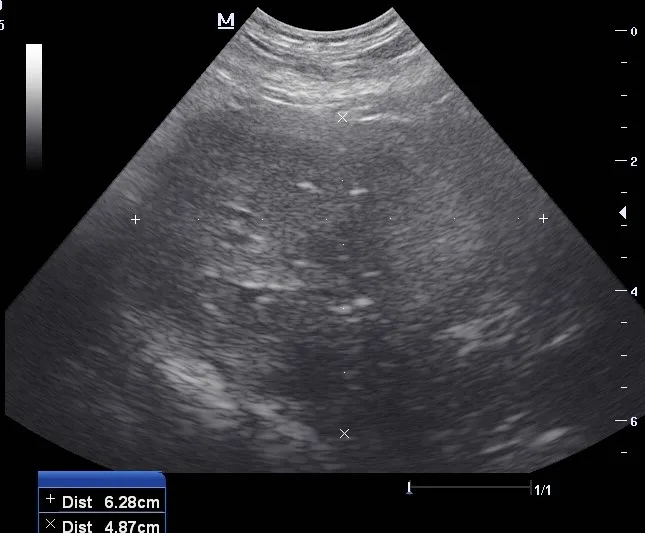

CBC and serum chemistry profile results were within normal limits, except for mildly elevated ALP (220 U/L; reference interval, 2-150 U/L). Transabdominal ultrasound showed an enlarged, heteroechoic prostate with multiple anechoic and hyperechoic foci, indicating a diagnosis of prostatitis (Figure).

Ultrasound images of the left (A) and right (B) prostate lobes. The prostate was enlarged and heteroechoic with multiple anechoic and hyperechoic foci.